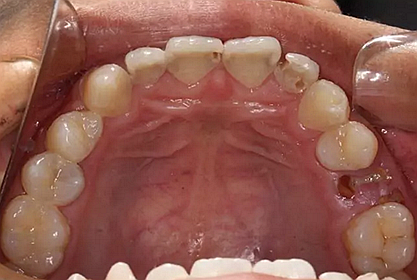

我們的主人今年才25歲,可卻從很小的時候就嗜好喝可樂等碳酸飲料,幾年下來,讓我們兄弟姐妹們整天浸在碳酸里受這蝕骨之痛,原本皎潔的外貌如今早己經(jīng)是腐蝕不堪、丑陋無比,更有甚者,一些兄弟姐妹們已經(jīng)病入膏肓,被病痛折磨奄奄一息。

下面是醫(yī)生眼中和ct下的我們

一身病痛啊

牙結(jié)石、牙齦炎癥、牙體殘缺、慢性牙髓炎、蛀牙......